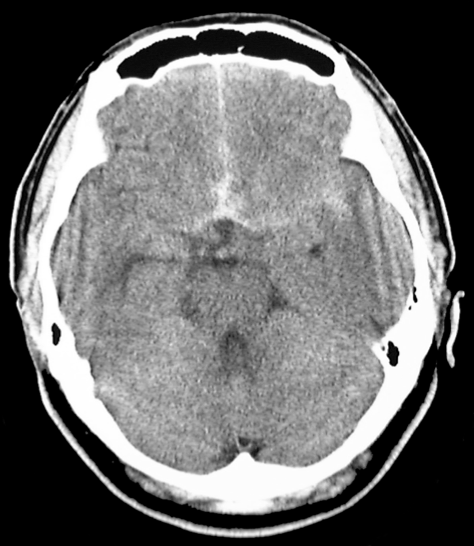

<頭部CT >

くも膜下出血の診断にはCTによるクモ膜下腔の高吸収の検出が適しており、発症24時間以内の診断率は92%で、以降時間の経過とともに低下します。すなわち、発症して救急車ですぐに病院に来られた場合には、診断率がよいということになりますが、2−3日経ってから(幸い再破裂などなく)、来院された場合には診断率が低下いたしますので、場合によってはCTのみでは診断ができない、誤診するということもありえるのです。

<典型的なくも膜下出血のCT画像>